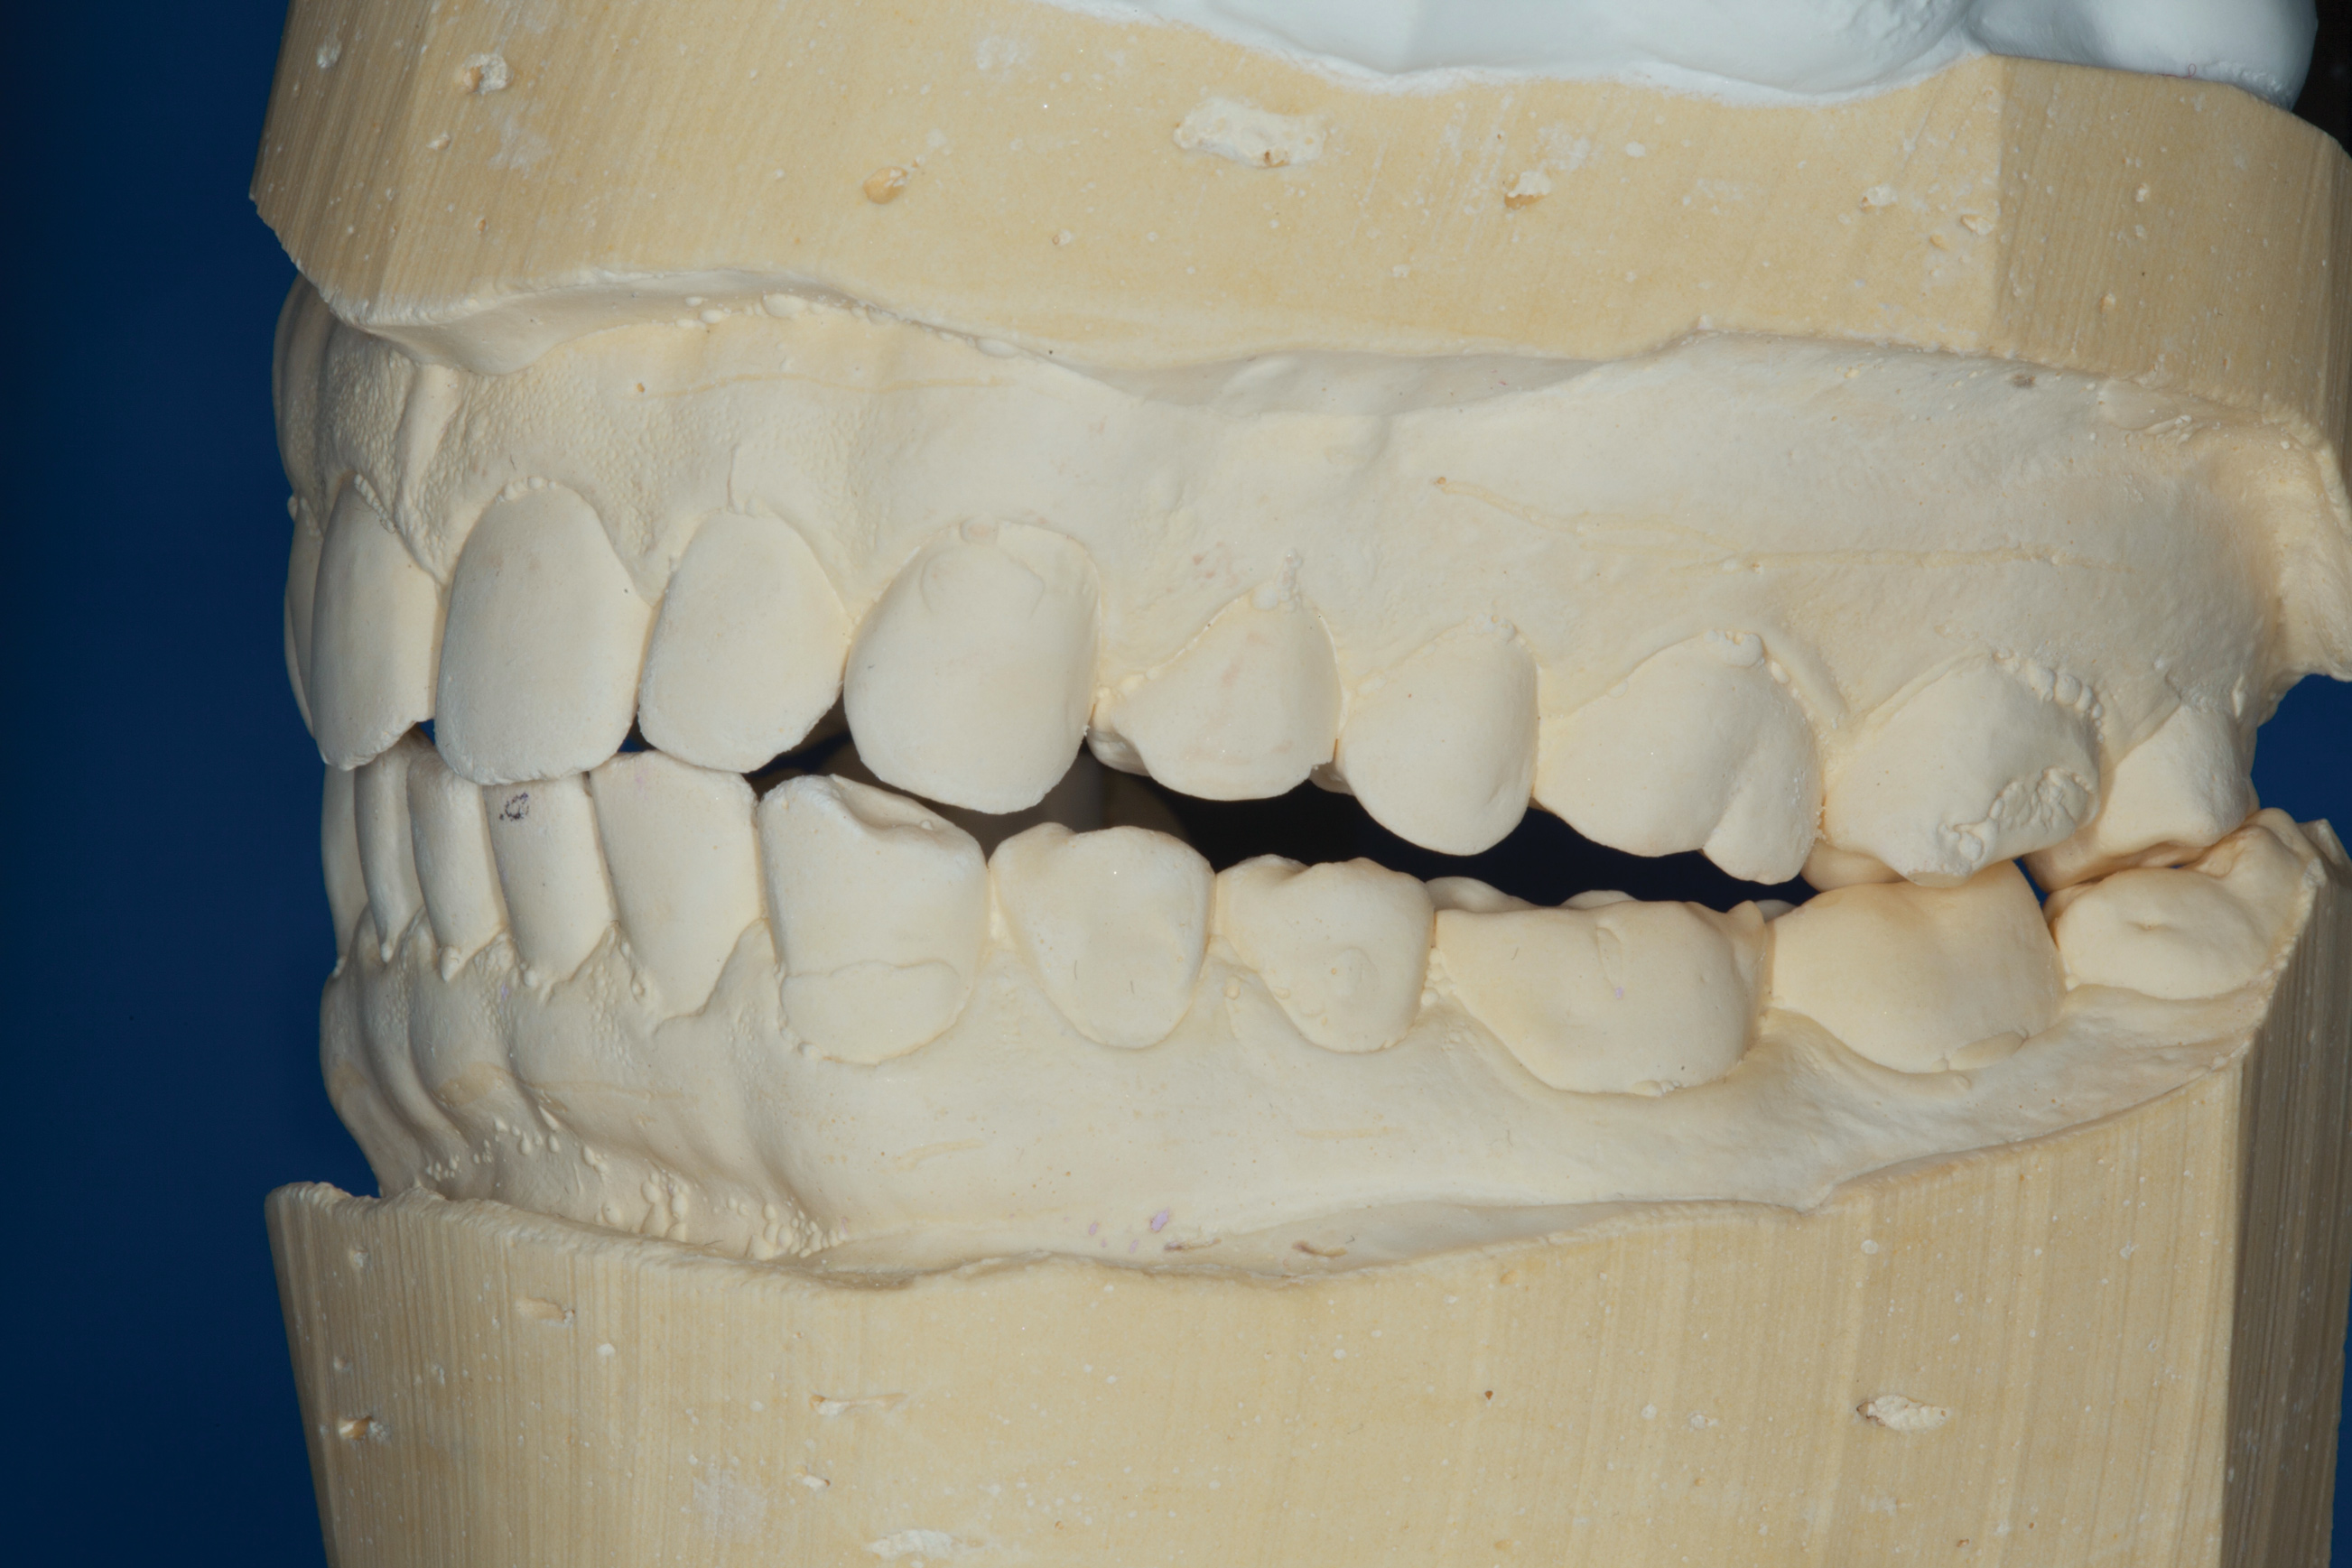

(5.) Mounted models showing maximum intercuspation.

Figure 5